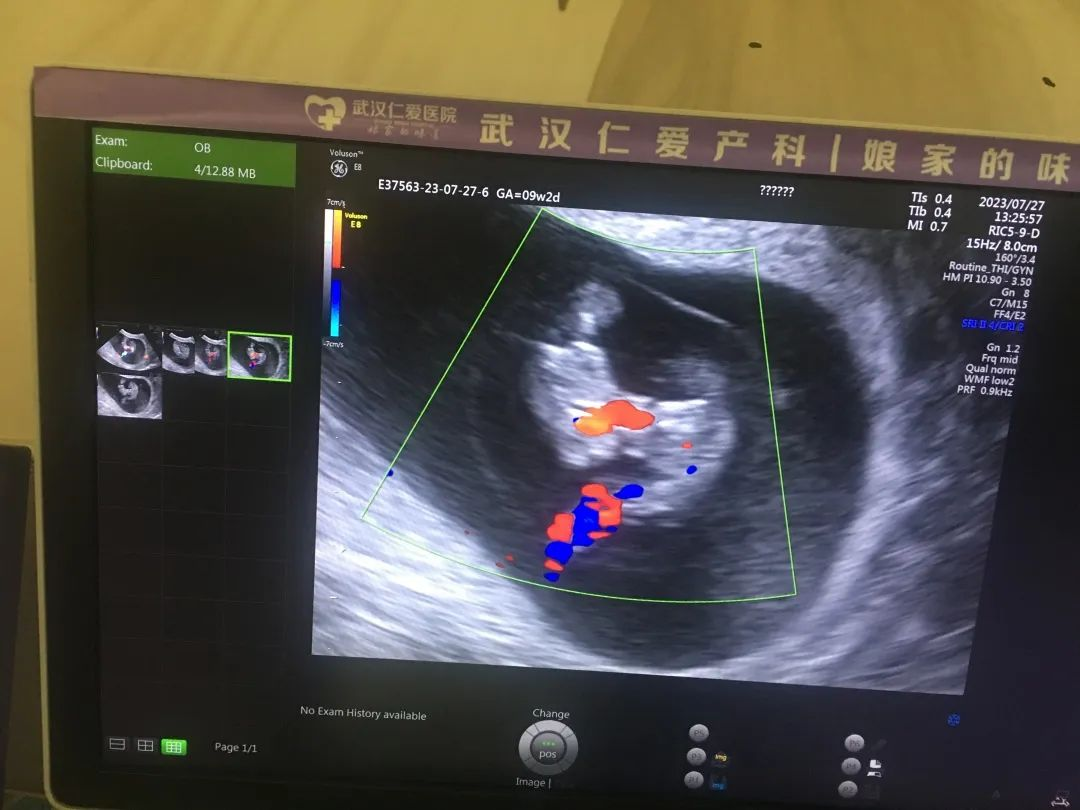

孕育一對(duì)雙胞胎,對(duì)于一個(gè)家庭來說,是件無比幸福的事。但在產(chǎn)科醫(yī)生的眼中,雙胎妊娠的孕婦屬于高危人群,單絨毛膜單羊膜囊雙胎更是所有雙胎妊娠中最高危的,因兩個(gè)胎兒共用一個(gè)胎盤、一個(gè)羊膜腔,但缺乏羊膜囊的分隔,兩個(gè)寶寶的臍帶容易纏繞或打結(jié),導(dǎo)致宮內(nèi)意外,風(fēng)險(xiǎn)極高。

“單絨單羊”雙胞胎發(fā)生率僅為十萬分之四,屬極其罕見又極其高危的雙胎妊娠。近日,武漢仁愛醫(yī)院超聲科就精準(zhǔn)為一位孕8周+的孕媽查出了“單絨毛膜單羊膜囊(MCMA)聯(lián)體雙胎”。